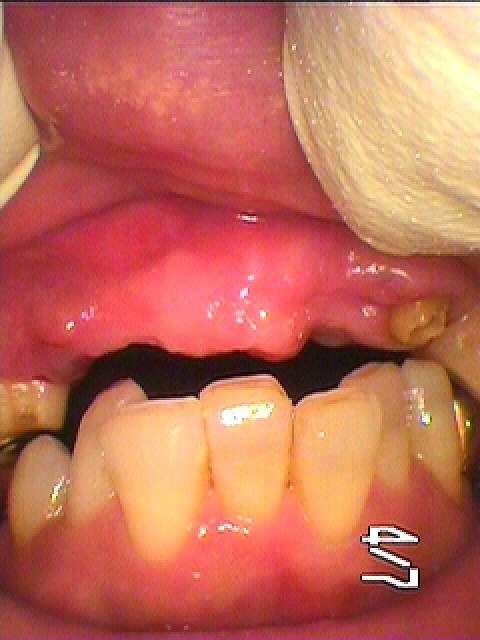

上顎前歯部の歯牙破折をもたらしたのも咬合によるものとも考えられます 咬合関係をかえていきます ジルコニアセラミッククラウン